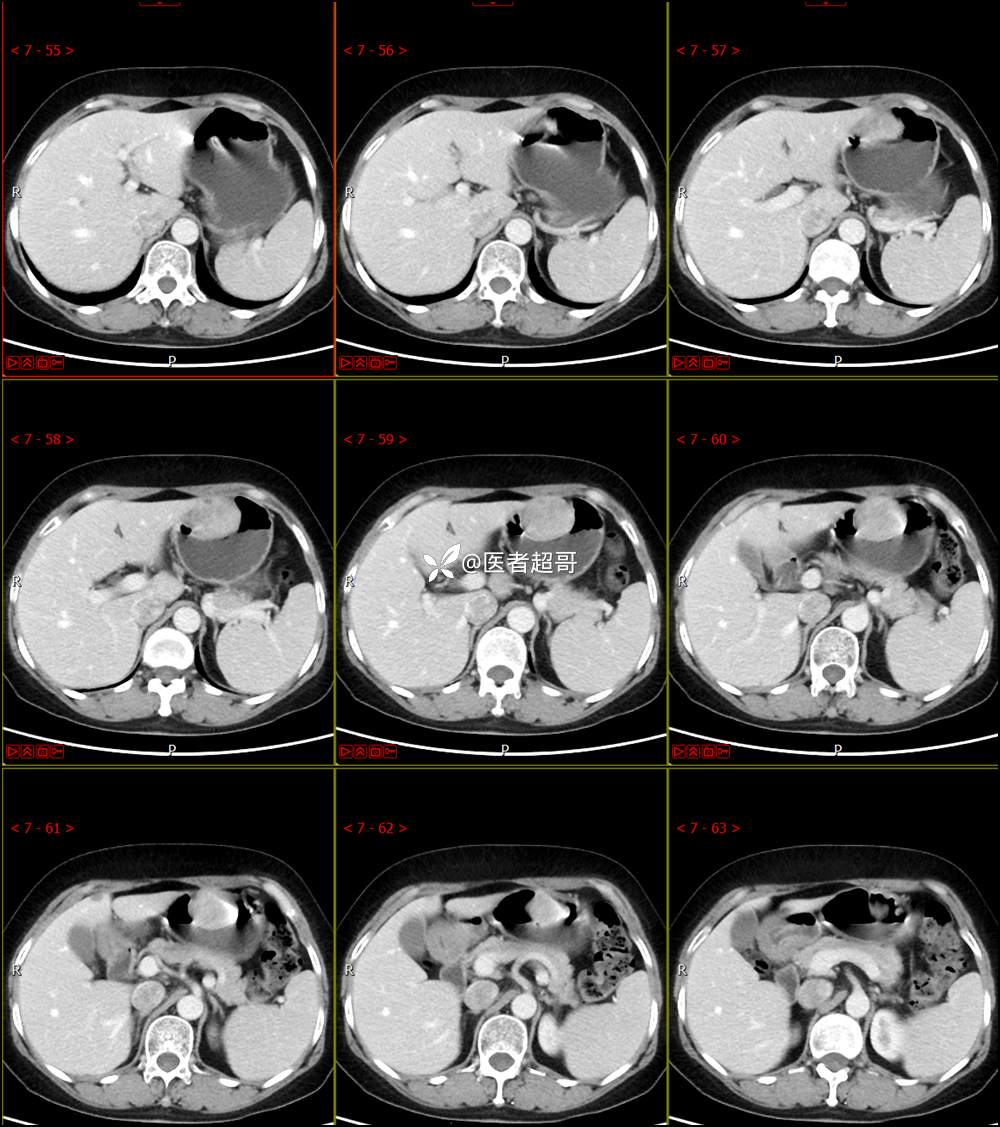

【影诊笔记759】胃体巨大隆起,间质瘤?神经鞘瘤?平滑肌瘤?请鉴别诊断!有结果!

患者半月前无明显原因及诱因出现上腹部疼痛不适,以夜间腹痛为主,无放射性疼痛,间断嗳气,无反酸烧心,无腹泻黑便,于我院门诊行胃镜显示:胃体前壁巨大隆起型病变。